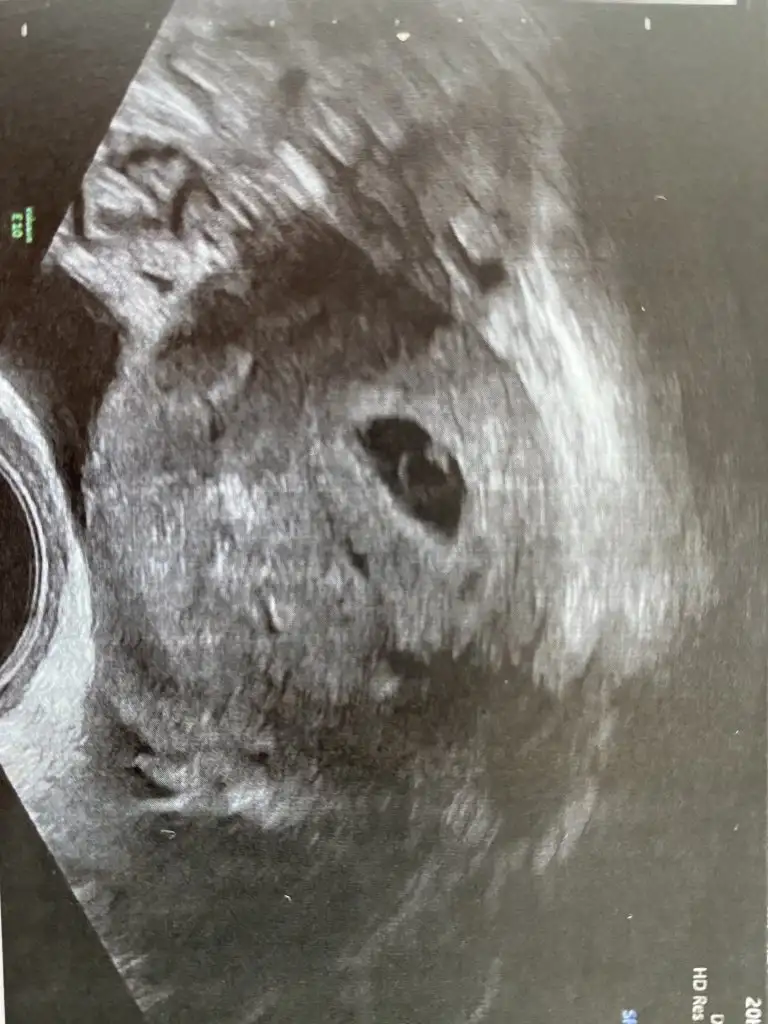

Ben dun hamile olduğumu ögrendim, kese göründü ve beta hcg 1640 cikti, bugün yine baktirdim, yani 24 saat sonra 2054,8 cikti… sizce normal mi? Veya düsük mu yapıyorum?

Evet. Keseyi de gördük. Bebeği de gördük çok şükür. darısı sana inşallahSizde benim gibi 5 haftalik hamilesiniz, hayirli olsunKeseyi gördunuz mu?